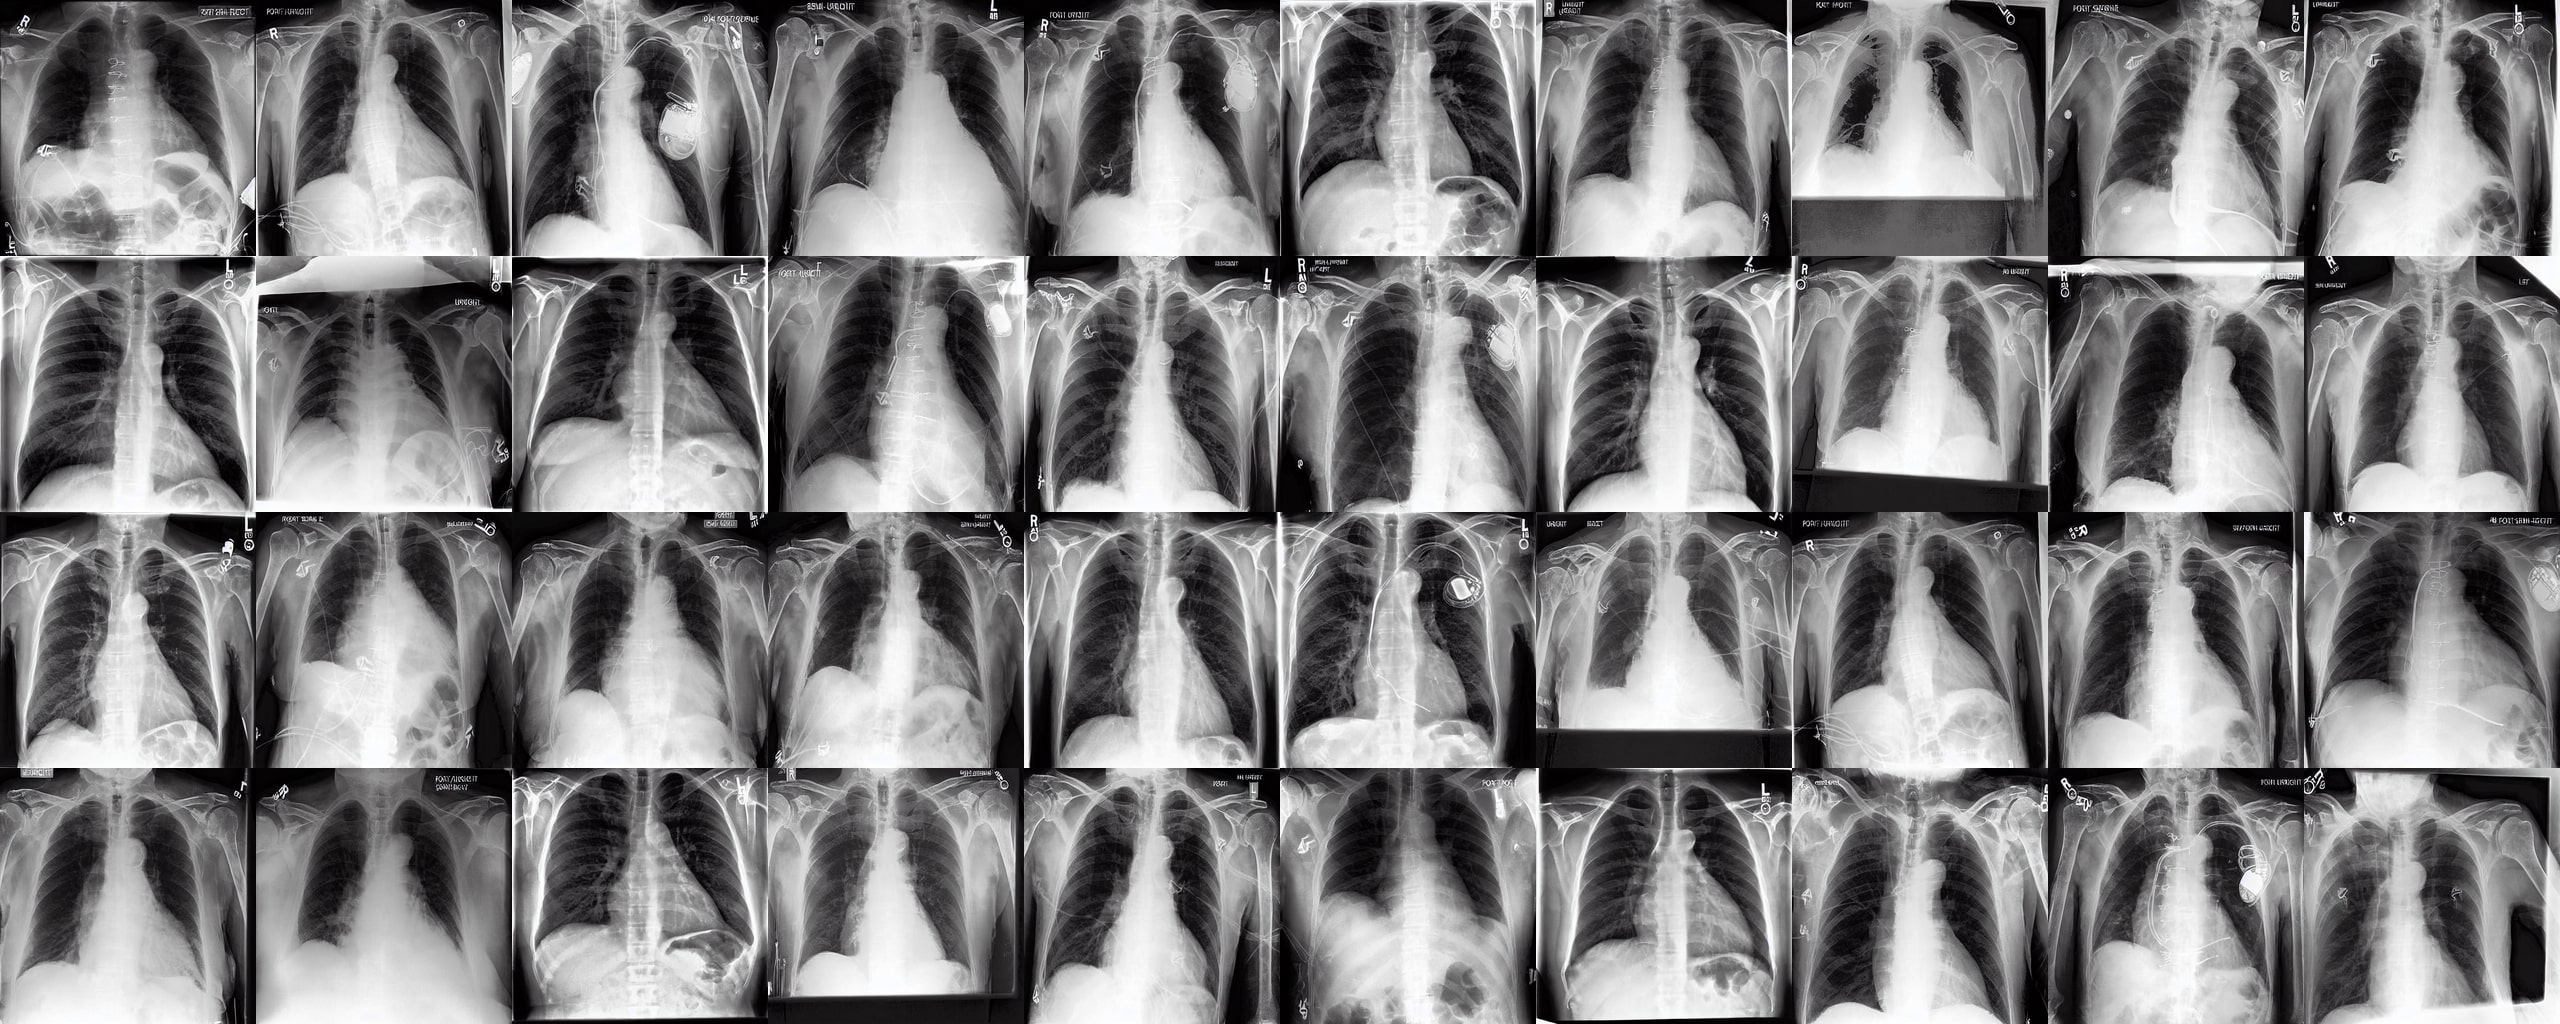

Chest X-rays We use the CheXpert dataset 10.1609/aaai.v33i01.3301590, which contains 170k training images. This dataset contains diversity in medical devices (such as chest tubes and wires), diseases (such as pneumonia and pleural-effusion) and anatomical details. We implement Rainbow on top of frozen parameters of a finetuned Stable Diffusion v1.5 (SD1.5) by previous work kumar2025prism for chest X-ray data. We generate 2D chest X-ray images based on text prompt conditions, e.g., "Chest X-ray showing Support Devices". In addition to the finetuned SD1.5, we include RadEdit perez2024radedit, a model trained from scratch on multiple chest radiology data such as CheXpert irvin2019chexpert, MIMIC-CXR johnson2019mimic, and NIH-CXR wang2017chestxray data for image editing tasks (more details at Appendix D.3), in the result comparison. Rainbow’s graph generator module includes , , and .

Chest X-rays Figure 4b quantifies generations by Rainbow and baselines using FID and VS. Rainbow achieves a higher VS, indicating greater diversity than the finetuned SD model, while also improving image quality with a lower FID score. Both Rainbow and SD outperform the RadEdit. Figure 6 provides a qualitative comparison, images are generated using the prompt "Chest X-ray showing support devices", where Rainbow generates a more diverse set of medical devices, such as pacemakers, in all generations, while baselines do not show any devices in some images. All models achieve similar CLIP scores of . Additional results including generations, Figure 22 and numeric results, Table 4, are outlined in Appendix E.

Chest X-rays To evaluate Rainbow on chest X-rays, we use FID and Vendi Score similar to the previous modalities. For feature extraction, we use a pre-trained DenseNet-121 [huang2017densely] model from the TorchXrayVision library [Cohen2022xrv], which is trained on multiple chest X-ray datasets such as CheXpert [irvin2019chexpert], NIH-CXR [wang2017chestxray], PadChest [bustos2020padchest], and MIMIC-CXR [johnson2019mimic]. The feature vectors used for calculating the metrics are extracted from the last layer (before the classifier head) with a dimensionality of 1024.

Chest X-rays We consider two chest X-ray baseline models. The first model is RadEdit [perez2024radedit], a latent diffusion model developed by Microsoft Health. This model is trained on 487,680 frontal view chest X-rays of multiple datasets such as MIMIC-CXR [johnson2019mimic], NIH-CXR [wang2017chestxray], and CheXpert [irvin2019chexpert]. The second baseline is a fine-tuned Stable Diffusion v1.5 model [kumar2025prism] on the CheXpert [irvin2019chexpert] dataset.